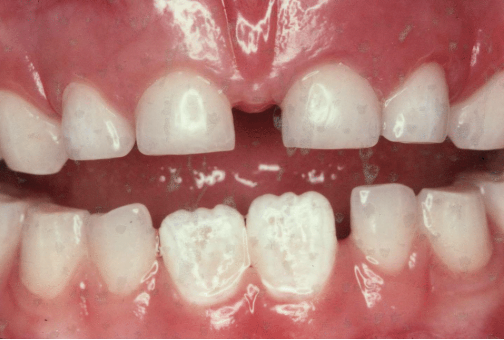

what age is this patient

6 or 7

which other permanent teeth should be present at this time

first permanent molars (6s)

what is the name given to the space between the upper central incisors

midline diastema

what has caused this in this particular case

low frenal attachment

what is the likely cause of the general appearacnnce of the lower central incisors

fluorosis

how is fluorosis likely to have arisen

excessive ingestion of fluoride during development of the teeth

what other permanent teeth are likely to affected by fluorosis

upper centrals

lateral incisors

canines

first premolars

second premolars

first molars

give 3 tx options for lower central incisors

microabrasion

composite restoration

strip crowns